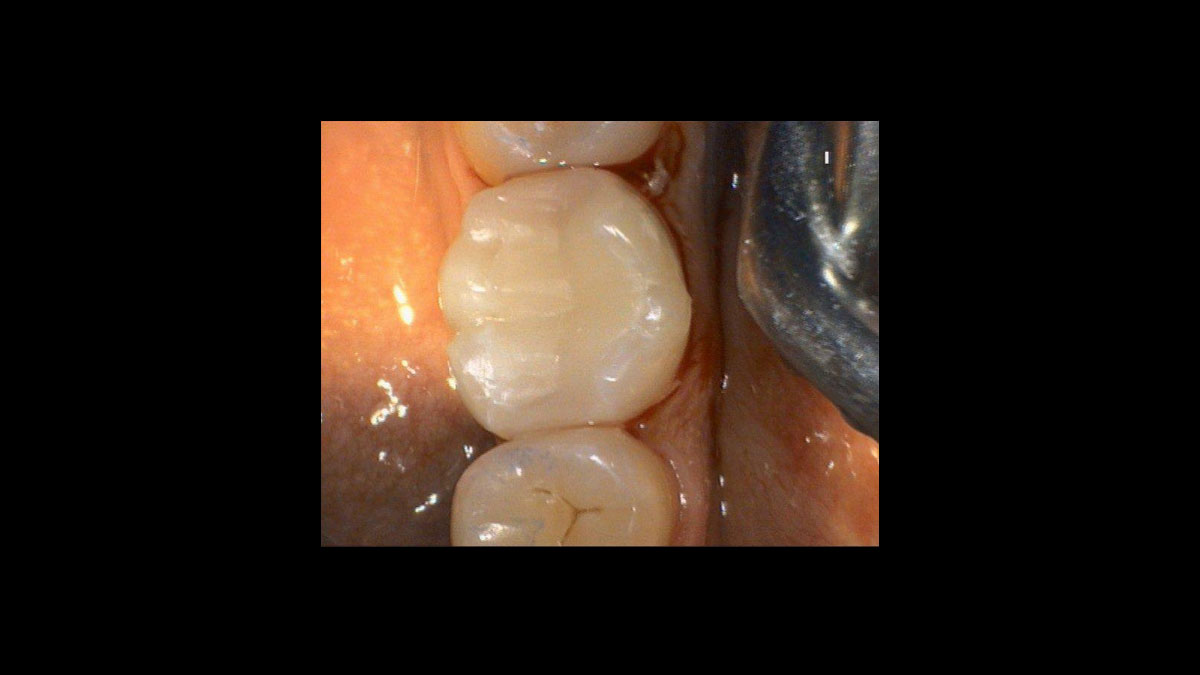

Implant uncovery